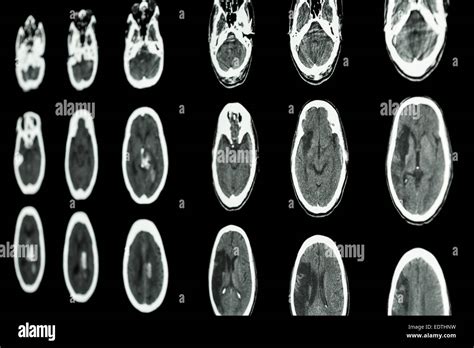

Before we jump into the details of the CT scan , let’s get on the same page about ischemic strokes. An ischemic stroke happens when the blood supply to the brain is cut off, usually because of a blood clot. This blockage starves the brain of oxygen and nutrients, leading to brain cell damage, and, if not treated quickly, this can result in permanent brain damage. Now, think of the brain as a complex network of highways and roads. The blood vessels are the highways delivering all the essential supplies, and if a roadblock (a clot) forms, traffic (blood flow) stops. The result? A stroke. Getting a quick diagnosis is super important. That’s where the CT scan comes into play. A CT scan, or computed tomography scan, is a type of imaging technique that uses X-rays to create detailed pictures of the inside of your body. Imagine taking a series of X-ray pictures from all angles, and then the computer puts them together to create a comprehensive, cross-sectional image. For the brain, this means doctors can see the structures in great detail, look for bleeding, and, most importantly, identify signs of an ischemic stroke .

Okay, so why is a CT scan so crucial? Well, when someone shows stroke symptoms (like sudden weakness, trouble speaking, or vision problems), doctors need to figure out what’s going on fast . The faster they can determine the cause of the stroke, the faster they can start treatment. A CT scan is often the first imaging test done because it’s quick, readily available in most hospitals, and can quickly rule out other possible causes of the symptoms. For instance, it can differentiate between an ischemic stroke and a hemorrhagic stroke (which is caused by bleeding in the brain), which is super important because the treatments are very different. In an ischemic stroke , the CT scan might show early signs of damage, such as subtle changes in the brain tissue, or it might reveal the absence of blood flow to certain areas. These early indications help doctors decide the best course of action. It can also help see if there’s any bleeding. It might not always show the stroke immediately, especially in the early hours. However, it’s still extremely valuable for ruling out other conditions and for helping doctors make a quick assessment.

In the early stages of an ischemic stroke , the CT scan might not show a lot of obvious changes. However, there are some subtle signs that experienced radiologists can spot. They look for the following signs:

• Loss of Grey-White Matter Differentiation: The brain is made up of grey matter and white matter, which have different densities. In the early stages of a stroke, the difference between these can become less clear, making it difficult to differentiate between them. This is often the first thing they notice.

• Hyperdense Artery Sign: Sometimes, the CT scan can show a blood clot as a very bright spot in an artery, known as the hyperdense artery sign. This is a telltale sign of a blood clot and helps to confirm the diagnosis.

• Subtle Swelling: The brain tissue may start to swell, and subtle changes in the density of the brain tissue. This can indicate that the brain is not getting enough blood.

Later Signs of Ischemic Stroke on a CT Scan

As time passes, the changes on the CT scan become more apparent. The following signs are usually visible later:

• Hypodensity: Areas of the brain that are damaged due to the lack of blood flow will start to appear darker on the CT scan. This is called hypodensity. It indicates that the brain tissue is dying.

• Mass Effect: As the brain swells, it can push on other structures, causing a mass effect.

• Infarct: This is a term for the area of dead tissue caused by the stroke. It can be seen as a clearly defined dark area on the scan.

Differentiating Ischemic vs. Hemorrhagic Stroke

One of the main goals of the CT scan is to differentiate between an ischemic stroke and a hemorrhagic stroke. A hemorrhagic stroke involves bleeding in the brain. On a CT scan, blood appears bright white. So, if the scan shows any bright white areas, it’s a sign of bleeding. If there’s no bleeding and the scan looks relatively normal (or shows the signs of ischemic stroke ), then it’s most likely an ischemic stroke . This distinction is super important because the treatments for each type of stroke are different.